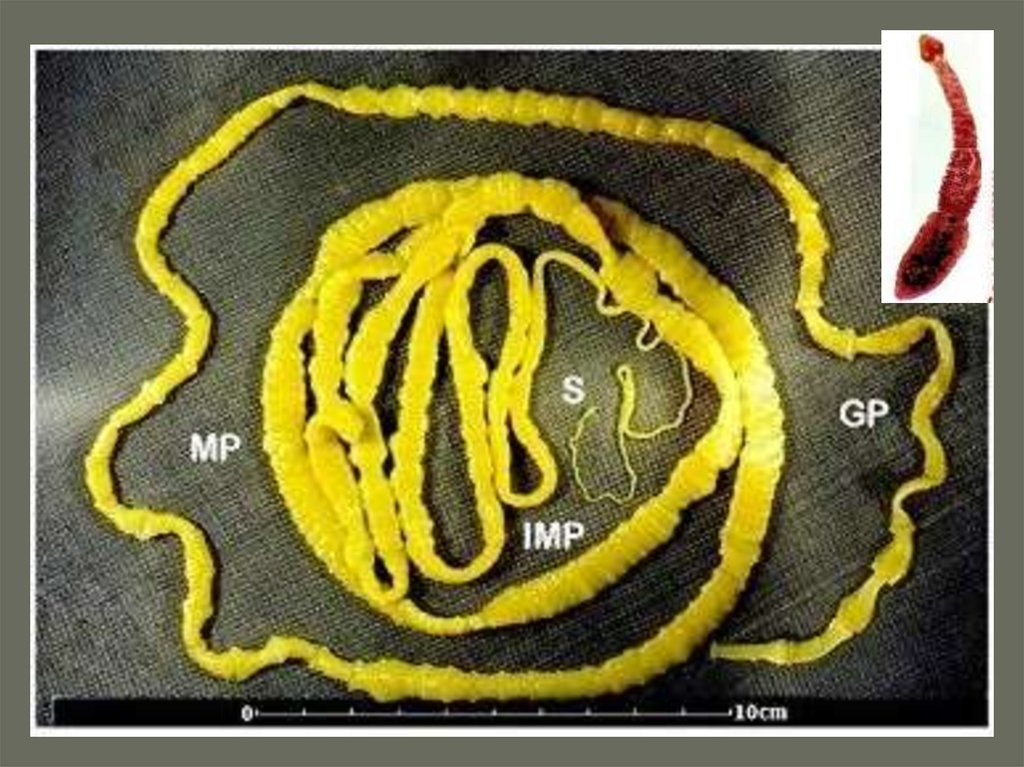

Фотографии нематод, цестод и трематод в природе